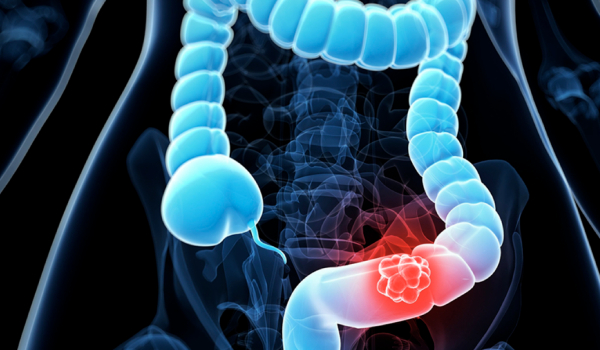

Tratamiento de apendicitis aguda, la diverticulitis, el prolapso rectal, el cáncer de colon

El cáncer colorrectal no cause síntomas enseguida.